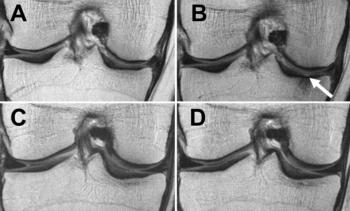

Figure 3. Baseline and follow-up MRIs of the knee of two obese women, one who lost no weight (A, B), and one who lost weight (C, D).

Cartilage degeneration was significantly lower in the weight loss group, compared to the control group over the 96 months. However, this finding was only present among the patients who lost weight through diet and exercise or diet alone. Although patients who only exercised lost as much weight as patients who dieted alone or dieted and exercised, weight loss through exercise alone showed no significant difference in cartilage degeneration, compared to the group who lost no weight.